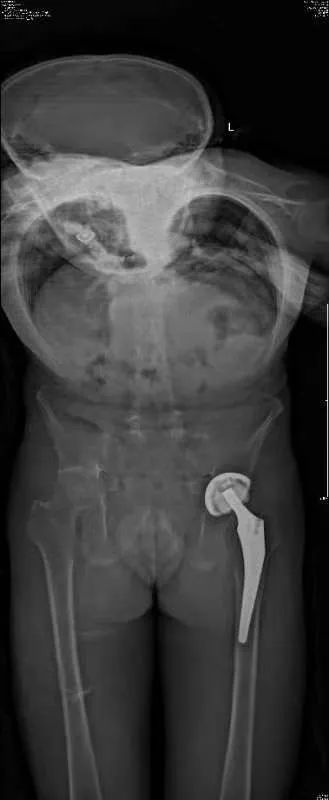

患者张先生(化名),10余年前确诊为强直性脊柱炎,间断口服药物治疗。10年前因此疾病在我院进行了全髋关节置换术,术后髋关节活动良好,那时脊柱没有出现畸形,还是可以直立的正常人。后来随着疾病的进展,脊柱后凸逐渐加重,于我院就诊时患者的胸腰椎后凸畸形已近90度,站立时的体态就如同鞠躬,睡觉无法平躺,严重影响生活质量。

患者又回到了最信任的北京积水潭医院,找到了髋关节手术的主刀医生周一新主任,由周主任介绍到脊柱外科。脊柱外科经过全科查房讨论,制定周密的术前规划,综合考虑患者的直立、平视、端坐、平躺等功能,设计截骨位置并计算截骨角度,最终确定了L3、T12双节段经椎弓根截骨的矫形方案。在麻醉科、手术室、肌电图室、ICU、输血科、脊柱外科等多方面合作下,手术顺利完成。患者术后即可完全平躺,下地后可完全直立并且平视。手术效果非常满意,患者重新挺起胸膛,开启新的人生。